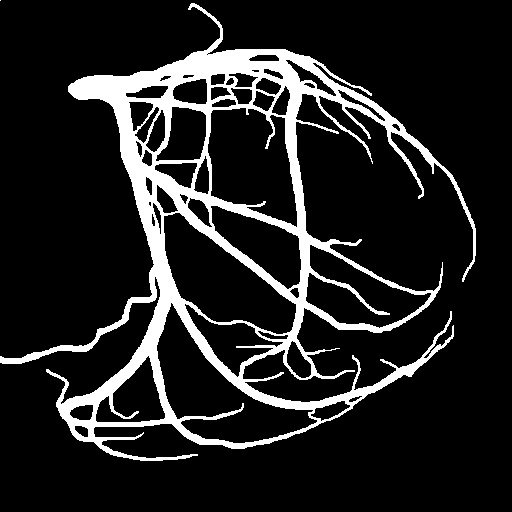

4.1 XACV Dataset

We collect 111 complete records of coronary artery X-ray videos, encompassing the injection, flow through the blood vessels around the heart, and dissipation of the contrast agent. Subsequently, we establish the XACV (X-ray Angiography Coronary Video) dataset. Each video consists of varying numbers of high-resolution coronary artery X-ray images. We invite experienced radiologists to annotate the vascular regions, focusing on one or two frames where the contrast agent is most prominent in each video. The XCAD dataset contains only a single image, and the CADICA video dataset does not provide corresponding ground truth. Therefore, in the following experiments, we conduct all the analyses on our collected XACV dataset and the corresponding GT for each sequence. In Figure 5, we show that compared to other publicly available datasets, XCAD [33] and CADICA [19], our dataset exhibits finer annotations in the vascular regions, providing an advantage for future related tasks. The development and use of our dataset have been approved by our institution’s IRB.